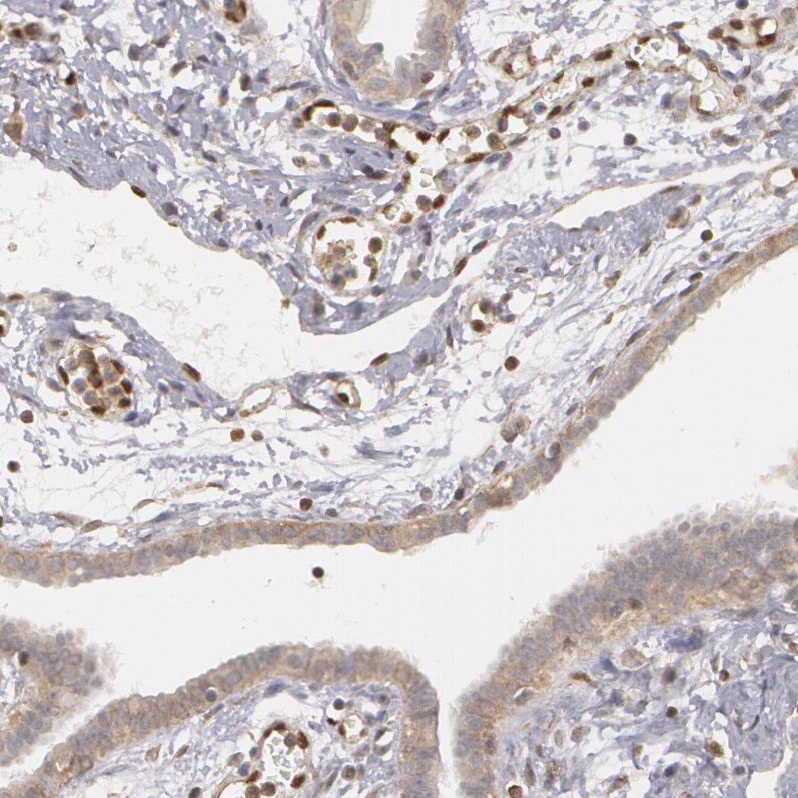

Immunohistochemical staining of human tonsil shows moderate nuclear positivity in lymphoid cells.